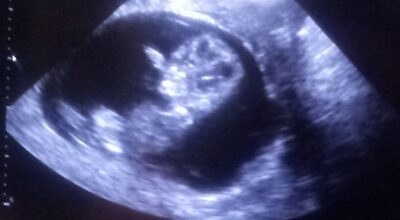

Isabella